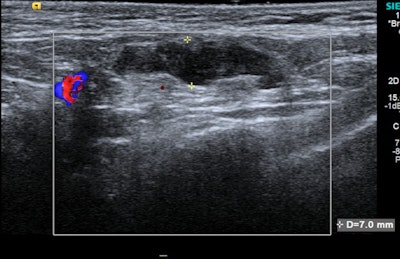

Ultrasound offers the most thorough assessment of the size and morphology of axillary lymph nodes due to its high soft-tissue resolution, according to the researchers. Sonographic changes seen in COVID-19 vaccine-related adenopathy include lymph node enlargement, a thickened cortex, and loss of the normal fatty hilum.